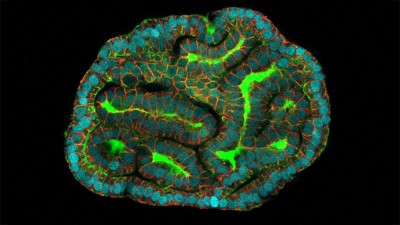

Organoids and spheroids are among the NAMs that can be generated from iPS cells or other cells. These 3D structures allow researchers to analyse cell behaviour, model diseases and test drugs in in vitro systems that mimic the architecture, function and cell types of a human organ, or the conditions provided by natural tissues.

An organoid made from cells found in the lining of the uterus. Credit: Konstantina Nikolakopoulou, Turco Lab, Friedrich Miescher Institute for Biomedical Research